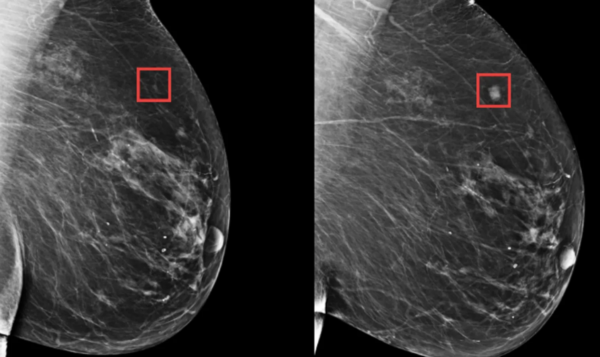

Anualmente se diagnostican alrededor de 2.3 millones de casos de cáncer de mama en todo el mundo, causando la muerte a unas 670 mil mujeres por esta enfermedad. “El cáncer de mama es la principal causa de muerte por cáncer en mujeres, a pesar de los despistajes con mamografías”, afirma Christiane Kuhl, directora del Departamento de Radiología del Hospital Universitario RWTH en Aquisgrán. La experta se refiere a las pruebas en personas sin síntomas, para poder detectar el cáncer en sus etapas iniciales. “La razón es que con la mamografía no podemos detectar tantos casos de cáncer de mama, o mejor dicho, no los detectamos lo suficientemente temprano”, añade. En particular, los tumores de crecimiento rápido y agresivo no suelen ser tan visibles en la mamografía, explica Kuhl. Además, son precisamente esos tumores los que provocan la muerte de muchas mujeres. AVANCE PROMETEDOR Ahora, un nuevo avance tecnológico promete mejorar la detección precoz del cáncer de mama. Se trata de un modelo de Inteligencia Artificial (IA) que con solamente analizar imágenes mamográficas puede clasificar con gran precisión el riesgo de cada persona en desarrollar cáncer de mama durante los próximos cinco años. Las mujeres a quienes el nuevo algoritmo clasificó como de alto riesgo desarrollaron cáncer de mama con mucha más frecuencia que aquellas a quienes la IA dio un resultado de “riesgo normal”. “Concretamente, las mujeres que fueron designadas como de alto riesgo desarrollaron cáncer de mama cuatro veces más a menudo que aquellas cuyo puntaje de la IA era bajo”, señala Christiane Kuhl, la principal autora del informe. “Con esta IA podemos predecir con mucha mayor precisión que una persona determinada desarrollará cáncer de mama en los próximos cinco años, basándonos en mamografías que parecen normales y no muestran ninguna señal de cáncer de mama”, añade la profesora Kuhl. MEJOR QUE LAS MAMOGRAFÍAS Actualmente se recomienda a mujeres de entre 50 y 75 años realizar una mamografía cada dos años para detectar el cáncer de mama. Sin embargo, los riesgos varían considerablemente de una mujer a otra. Christiane Kuhl aboga por una prevención individualizada del cáncer de mama, ya que la precisión de la mamografía también difiere mucho entre las mujeres. Cuanto más denso es el tejido glandular mamario, mayor es el riesgo de padecer esa enfermedad y peor es la capacidad de la mamografía para predecir dicho riesgo. Muchas mujeres desconocen esto, critica Kuhl. Desde hace algunos años se recomienda ofrecer a las mujeres con tejido mamario extremadamente denso una resonancia magnética (RM) para la detección precoz, que ayuda a identificar el cáncer de mama de manera fiable y temprana. Para identificar a las mujeres que necesitan una RM para la detección precoz, el Consorcio Clairity, una asociación internacional de 46 centros de investigación en Estados Unidos, Canadá, Sudamérica y Alemania, ha desarrollado el sistema de IA Clairity Breast. PRECISIÓN EN LA DETECCIÓN PRECOZ Para que el modelo de IA pueda determinar el riesgo de cáncer de mama, el algoritmo fue entrenado con cientos de miles de mamografías procedentes de Norteamérica, Sudamérica y Europa. A diferencia de los modelos clásicos de riesgo, el algoritmo no necesita información sobre antecedentes familiares, genética o estilo de vida. Calcula exclusivamente a partir de la mamografía la probabilidad de cáncer de mama y clasifica a las mujeres en categorías de riesgo según umbrales definidos. La IA no solo reconoce la cantidad de tejido glandular, sino también su textura, es decir, cómo está dispuesto el tejido, otro parámetro que calcula el riesgo de cáncer de mama. “Solo alrededor del 10 por ciento de las mujeres tienen un tejido glandular extremadamente denso”, explica Kuhl. “La mayoría de las mujeres que desarrollan cáncer de mama y reciben un diagnóstico tardío tienen un tejido menos denso”, explica. Para ella, el avance decisivo es que “la IA puede decidir en cuestión de segundos si una mujer necesita una RM para la detección precoz o no”. INICIAR PREVENCIÓN ANTES El despistaje de cáncer de mama comienza en la mayoría de los países a partir de los 50 años, porque el riesgo aumenta significativamente con la edad y el beneficio de un despistaje generalizado a partir de esa edad está estadísticamente demostrado. Las mujeres más jóvenes enferman con menor frecuencia que las mayores, pero cuando lo hacen desarrollan con mayor frecuencia tumores agresivos. “De hecho, las mujeres jóvenes se beneficiarían especialmente de la detección precoz, siempre que esta funcione”, afirma Kuhl. EVALUACIÓN DE RIESGOS DIRIGIDA Christiane Kuhl considera poco útil reducir de forma generalizada la edad de inicio del despistaje. “Si simplemente bajamos la edad de las mujeres invitadas al cribado mamográfico, no estamos cambiando nada del problema fundamental”. En su lugar, aboga por un procedimiento en dos pasos: “Primero la mamografía para la detección precoz; después debería realizarse un análisis mediante IA para determinar el riesgo de enfermedad en los próximos cinco años”. Si el algoritmo indica un riesgo especialmente alto, debe ofrecerse una RM. “En estas mujeres la mamografía ya no es necesaria”, subraya la autora principal Christiane Kuhl. (Texto y fotos: Tomados de DW Español) Compartir Navegación de entradas Reducen ira política bloqueando contenidos en la red X Hallazgo “excepcional” en Egipto revela secreto olvidado